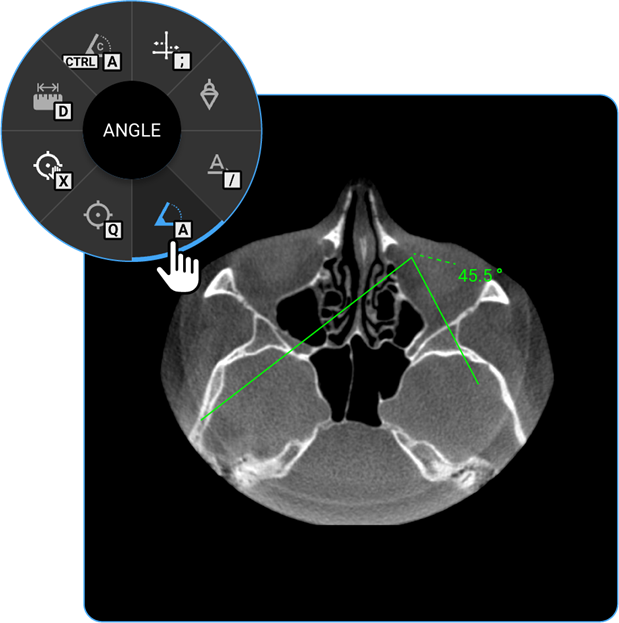

- Angle: Click on the Angle tool to determine the angle between two intersecting lines, assisting in anatomical evaluations.